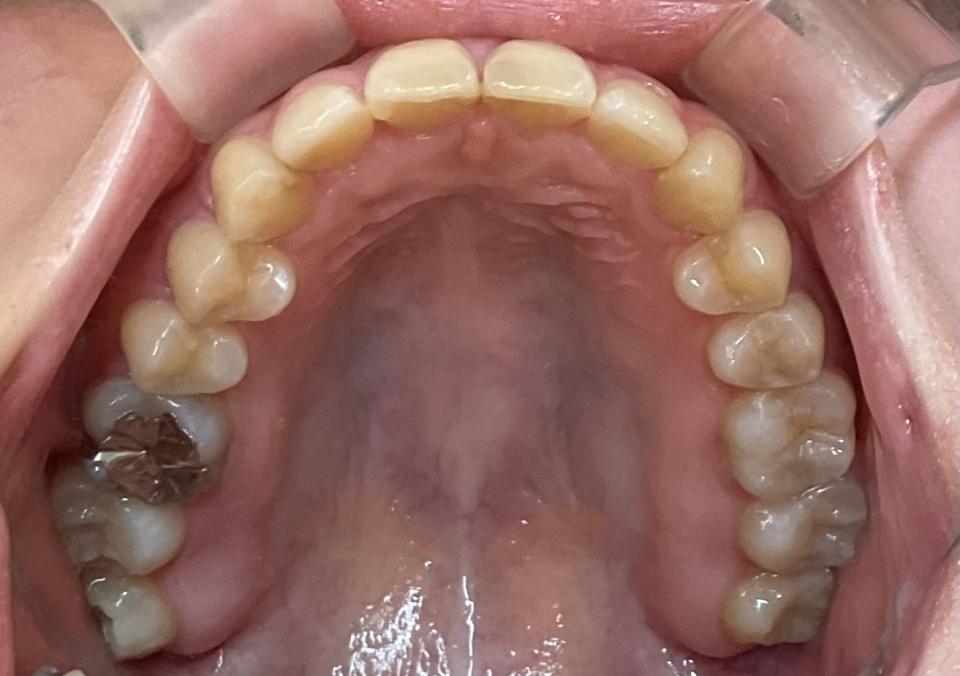

がたがた(叢生)の部分的なマウスピース矯正治療例

矯正治療前

20代女性の患者さんです。

右上前歯の捻じれと隙間を気にして来院されました。

部分的な矯正治療を希望され、

マウスピース型の矯正治療装置を使用し、歯のやすり掛け(IPR)を行いました。